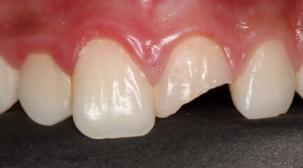

单纯的牙冠折断,医生通过“补牙”的方式就可以恢复我们牙齿的正常外形。

术前:

橡皮障下修复治疗中:

修复术后: